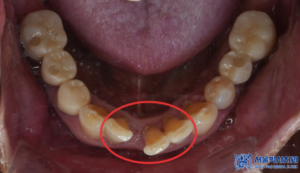

환자분은 아래쪽 앞니가 빠지면서

음식물을 씹기가 불편한 것은 물론이고,

사람을 마주하기가 어려워

치료를 고민하고 계시다 지인의 소개로

신흥동치과 서울박사치과를 찾아주셨는데요.

앞니가 빠진 부위뿐만 아니라 전체적으로

상태가 좋지 않은 치아들이 많았고,

몇몇 치아는 염증이 심한 상태였습니다.

특히 아래쪽 앞니 부위는 오랜 기간 치아가

빠져 있던 탓에 뼈가 많이 흡수된 상태였습니다.